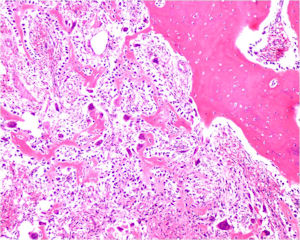

Microscopic Pathology

- Interlacing network of bone trabeculae in a loose fibrovascular stroma

- Prominent vessels

- Osteoblasts are plump, active, scattered mitotic figures

- Osteoblasts line up around periphery of trabeculae (Osteoblastic Rimming)

- Soft tissue component usually surrounded by shell of reactive bone or periosteum (Egg Shell Rim of Calcification)

- No cartilage production (as opposed to osteosarcomas that may contain areas of cartilage)